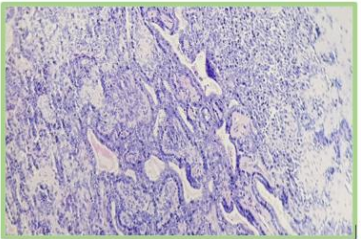

Figure 7: HE*4 benign tumor proliferation suggesting a pleomorphic adenoma of the parotid gland.

Figure 8: HE*20 pleomorphic adenoma of the parotid gland.